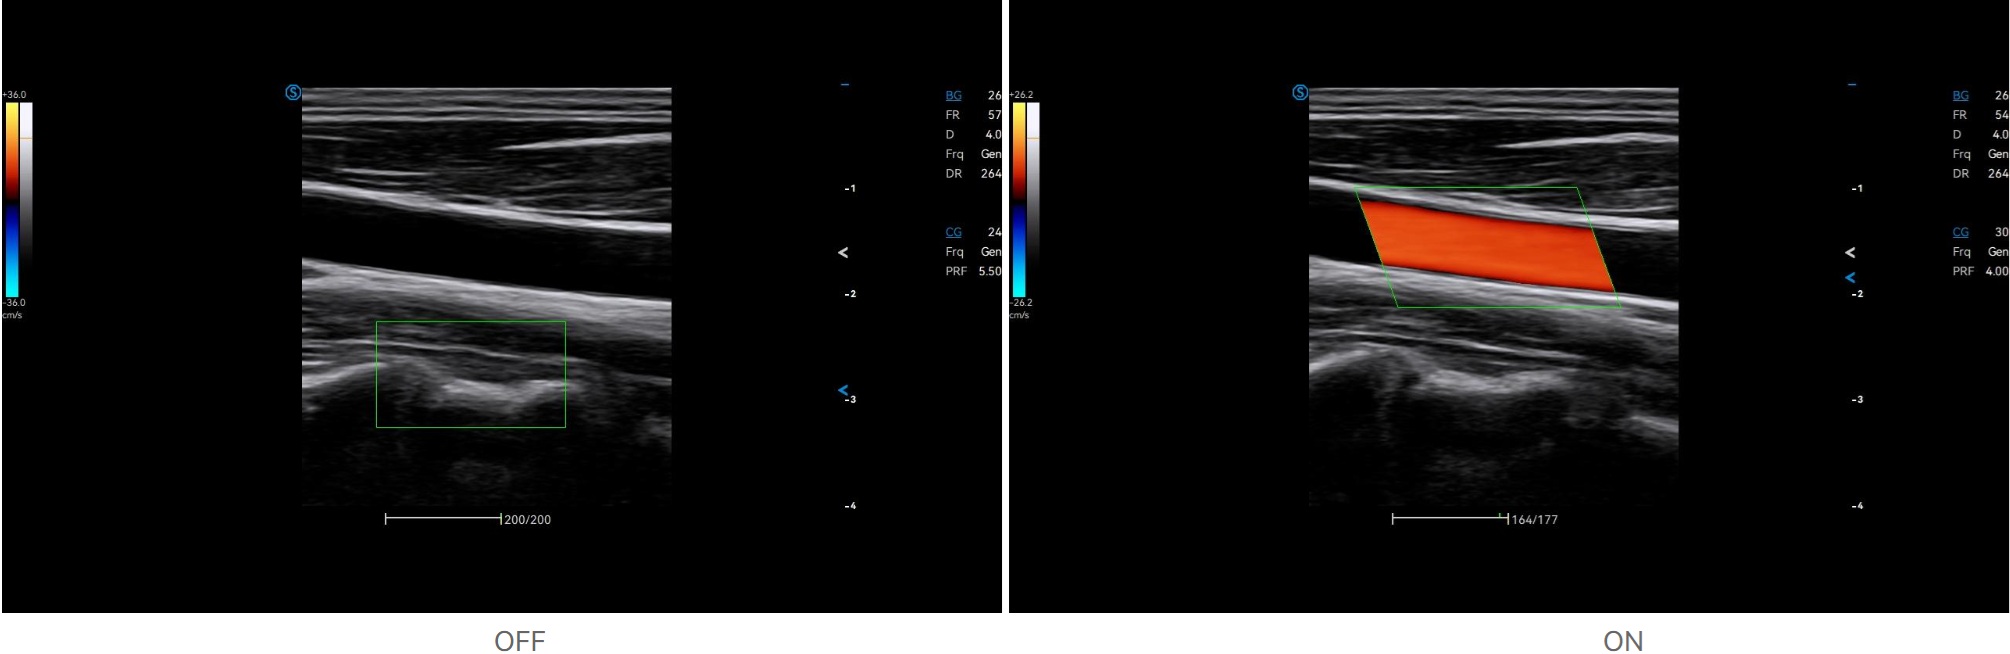

VS Flow is highly sensitive to low velocity blood flow signal and especially suitable for superficial blood flow examination

Auto Flow automatically adjusts the sampling frame to better capture the blood flow signal, while Auto Fit intelligently optimizes the image display through one click